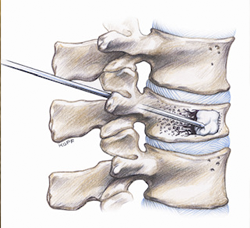

VERTEBROPLASTIA

La vertebroplastia consiste en poner cemento dentro de la vértebra para que esta no siga aplastándose.

La vertebroplastia es una técnica mínimamente invasiva que se realiza con una incisión menor de 1 cm que puede realizarse con anestesia local y sedación.

La vertebroplastia está indicada para tratar aquellos aplastamientos vertebrales que son dolorosos después de 8 semanas.

La vertebroplastia mejora el dolor porque por un lado endurece la vértebral, pero también tienen un efecto tóxico sobre las terminaciones nerviosas inutulizandolas de manera que no transmiten el dolor. También parece que el calor que produce el cemento al endurecerse afectaría a las fibras nerviosas que transmiten el dolor.

CIFOPLASTIA

La cifoplastia es similar a la vertebroplastia, también en esta técnica vamos a introducir cemento, pero antes de hacerlo hincharemos un balón en el interior de la vértebra para dejar espacio al cemento. Al hinchar el balón conseguimos compactar el hueso y recuperar la altura de la vértebra.